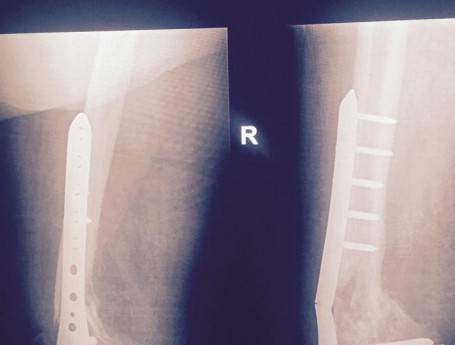

Total Knee Arthroplasty After a non-union

Revision Total Knee Replacement After a fructure